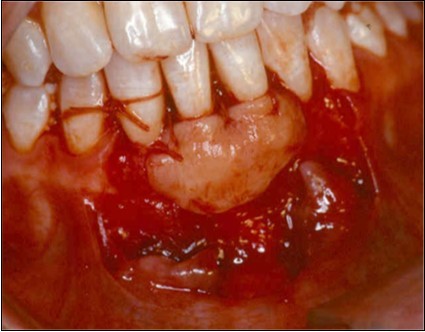

Donor Site

A second surgical site is created on the palate. The length of this is determined by the combines width of the teeth to be covered. The incisions are made in an anterior posterior direction. They are carried to the depth of the palatal mucosa, where they converge just short of the bone. A wedge of tissue is removed as free gingival graft, and its band of epithelium is excised by using Er:YAG laser and acute dissection with scalpel and blade 15C (Figure 4, Figure 4A). The graft is placed in the previously recipient site so that it completely covers the formerly exposed root area (Figure 5). It is then firmly sutured in place with 5-0 gut. The partial thickness, flap is positioned coronally in a manner to cover as much of the graft as possible and sutured in this position to promote maximum adaptation to ensure better healing with less chance of wound dehiscence (Figure 6). The donor site and recipient site is covered with surgical dressing and the patient is instructed in normal postsurgical management. The patient is seen on the 7th postoperative day to remove the surgical dressing and sutures. No additional dressing is necessary, and normal plaque control techniques are resumed (Figure 7)

Figure 4.Donor site area in the palate

Donor site area in the palate